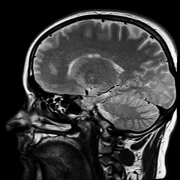

• 小兒腦干膠質(zhì)瘤mr表現(xiàn)?腦干膠質(zhì)瘤引起的頭疼癥狀

小兒腦干膠質(zhì)瘤mr表現(xiàn) 1、頭顱CT:頭部CT可以顯示腦干部位是否存在低密度或等密度占用,也可以顯示混合密度,腫瘤多實(shí)性少囊變不均勻強(qiáng)化。腫瘤的顯...

腦干膠質(zhì)瘤病理檢查怎么做 1、CT檢查:利用X線束掃描人體某個(gè)部位的某個(gè)厚度。主要用于急診患者,或者有MRI檢查禁忌的患者。根據(jù)圖像結(jié)果觀察是否有腫...